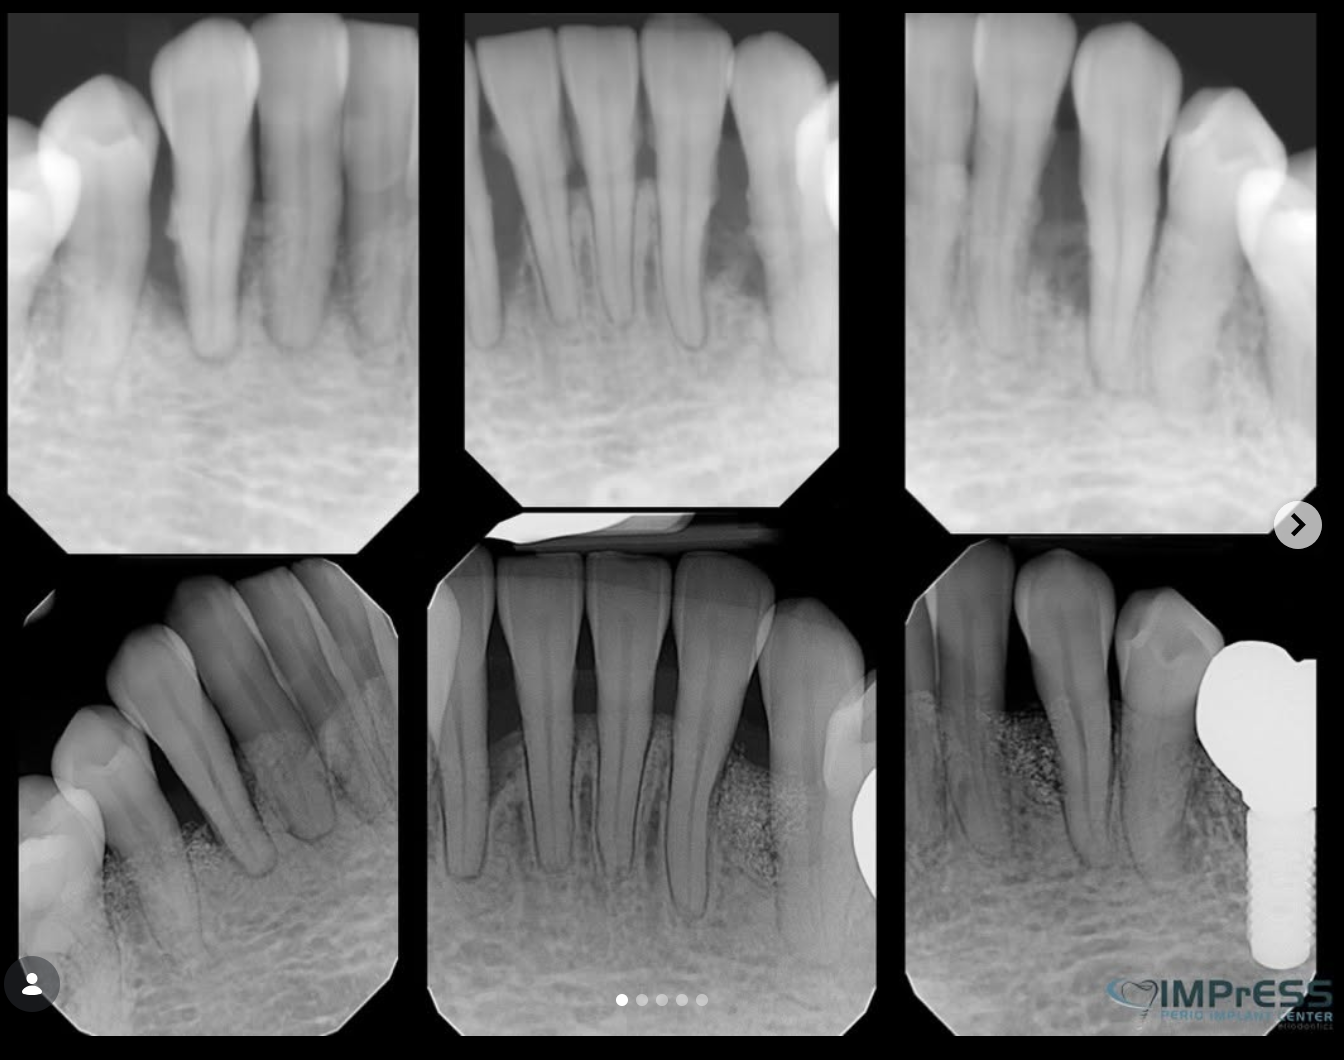

As periodontal disease progresses, pockets of degenerated bone develop in the jaw. These pockets can promote the growth of bacteria and the spread of infection. To address these pockets, Drs. Noroozi or Pauletto may recommend tissue regeneration. During this surgical procedure, the pockets are cleaned thoroughly, and a membrane is installed between the soft tissue and the pocket in the bone. Some of these membranes are bio-absorbable and some require removal. The membrane covers the pocket so that fast-growing soft tissue is blocked, and slower-growing bone can begin to grow, or “regenerate” itself.

Guided Bone/Tissue Regeneration Procedures that regenerate lost bone and tissue supporting your teeth can reverse some of the damage caused by periodontal disease. Your periodontist may recommend a regenerative procedure when the bone supporting your teeth has been destroyed due to periodontal disease. These procedures can reverse some of the damage by regenerating lost bone and tissue.

During this procedure, your periodontist folds back the gum tissue and removes the disease-causing bacteria. Membranes (filters), bone grafts or tissue-stimulating proteins can be used to encourage your body’s natural ability to regenerate bone and tissue. Eliminating existing bacteria and regenerating bone and tissue helps to reduce pocket depth and repair damage caused by the progression of periodontal disease.